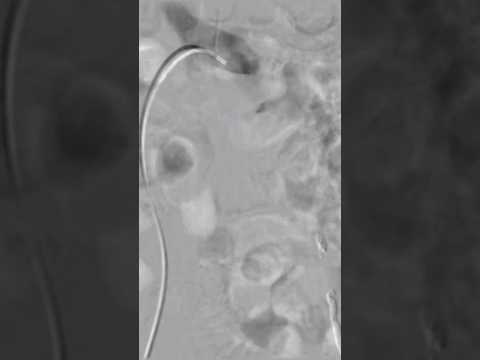

Varicocoele embolisation